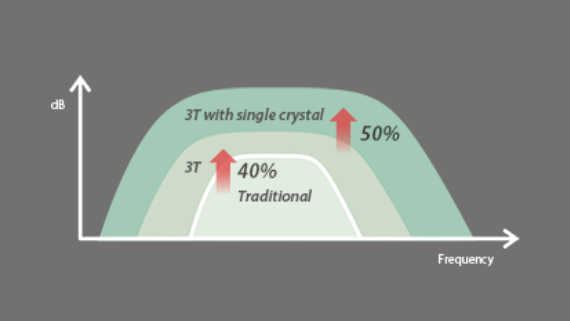

Transductores